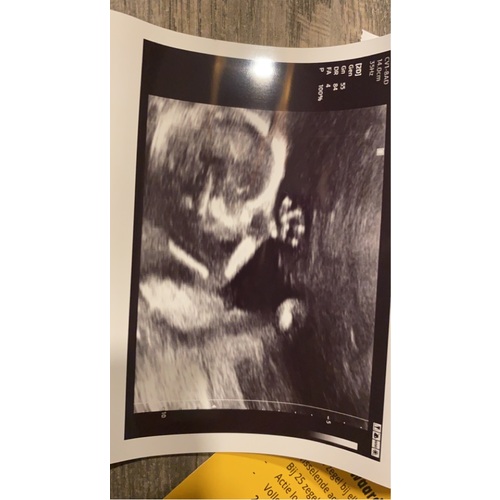

Ik ben nu 17+4 zwanger van een jongetje.